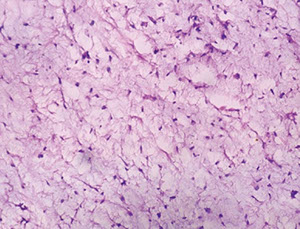

Acinic Cell Carcinoma

Malignant neoplasm with cells resembling normal serous acinar cells;

Parotids(4/5) > Submandibular > Minor salivary glands, F>M

Variable architecture (types) and cell morphology

Clear cytoplasm generally, but can be solid or vacuolated

- if cytoplasmic vacuoles present, may stain PAS (+); however they are just secretory granules and not mucin (as in MEC)

- usualy basophilic c lots of lymphoid infiltrate

- can look a little like thyroid

Can be in sheets or microcystic, glandular, follicular or papillary patterns

Usually few mitoses and little anaplasia

IHC: (+) PAS, PASD, (clear cells are PAS and mucin neg), keratin, amylase, transferrin, IgA, proline-rich protein, ANO1 (anoctamin-1)/DOG1 (Discovered On GIST-1), SOX10

- Negative GCDFP-15, MUC1, BRST-2 and mammaglobin and HER2

Clinical course dependent of degree of pleomorphism, though not well established

10-15% with LN mets, up to 35% recurrence

Both associated with worse prognosis

- otherwise fairly good 5-year survival (low-risk)

Acinic cell carcinoma